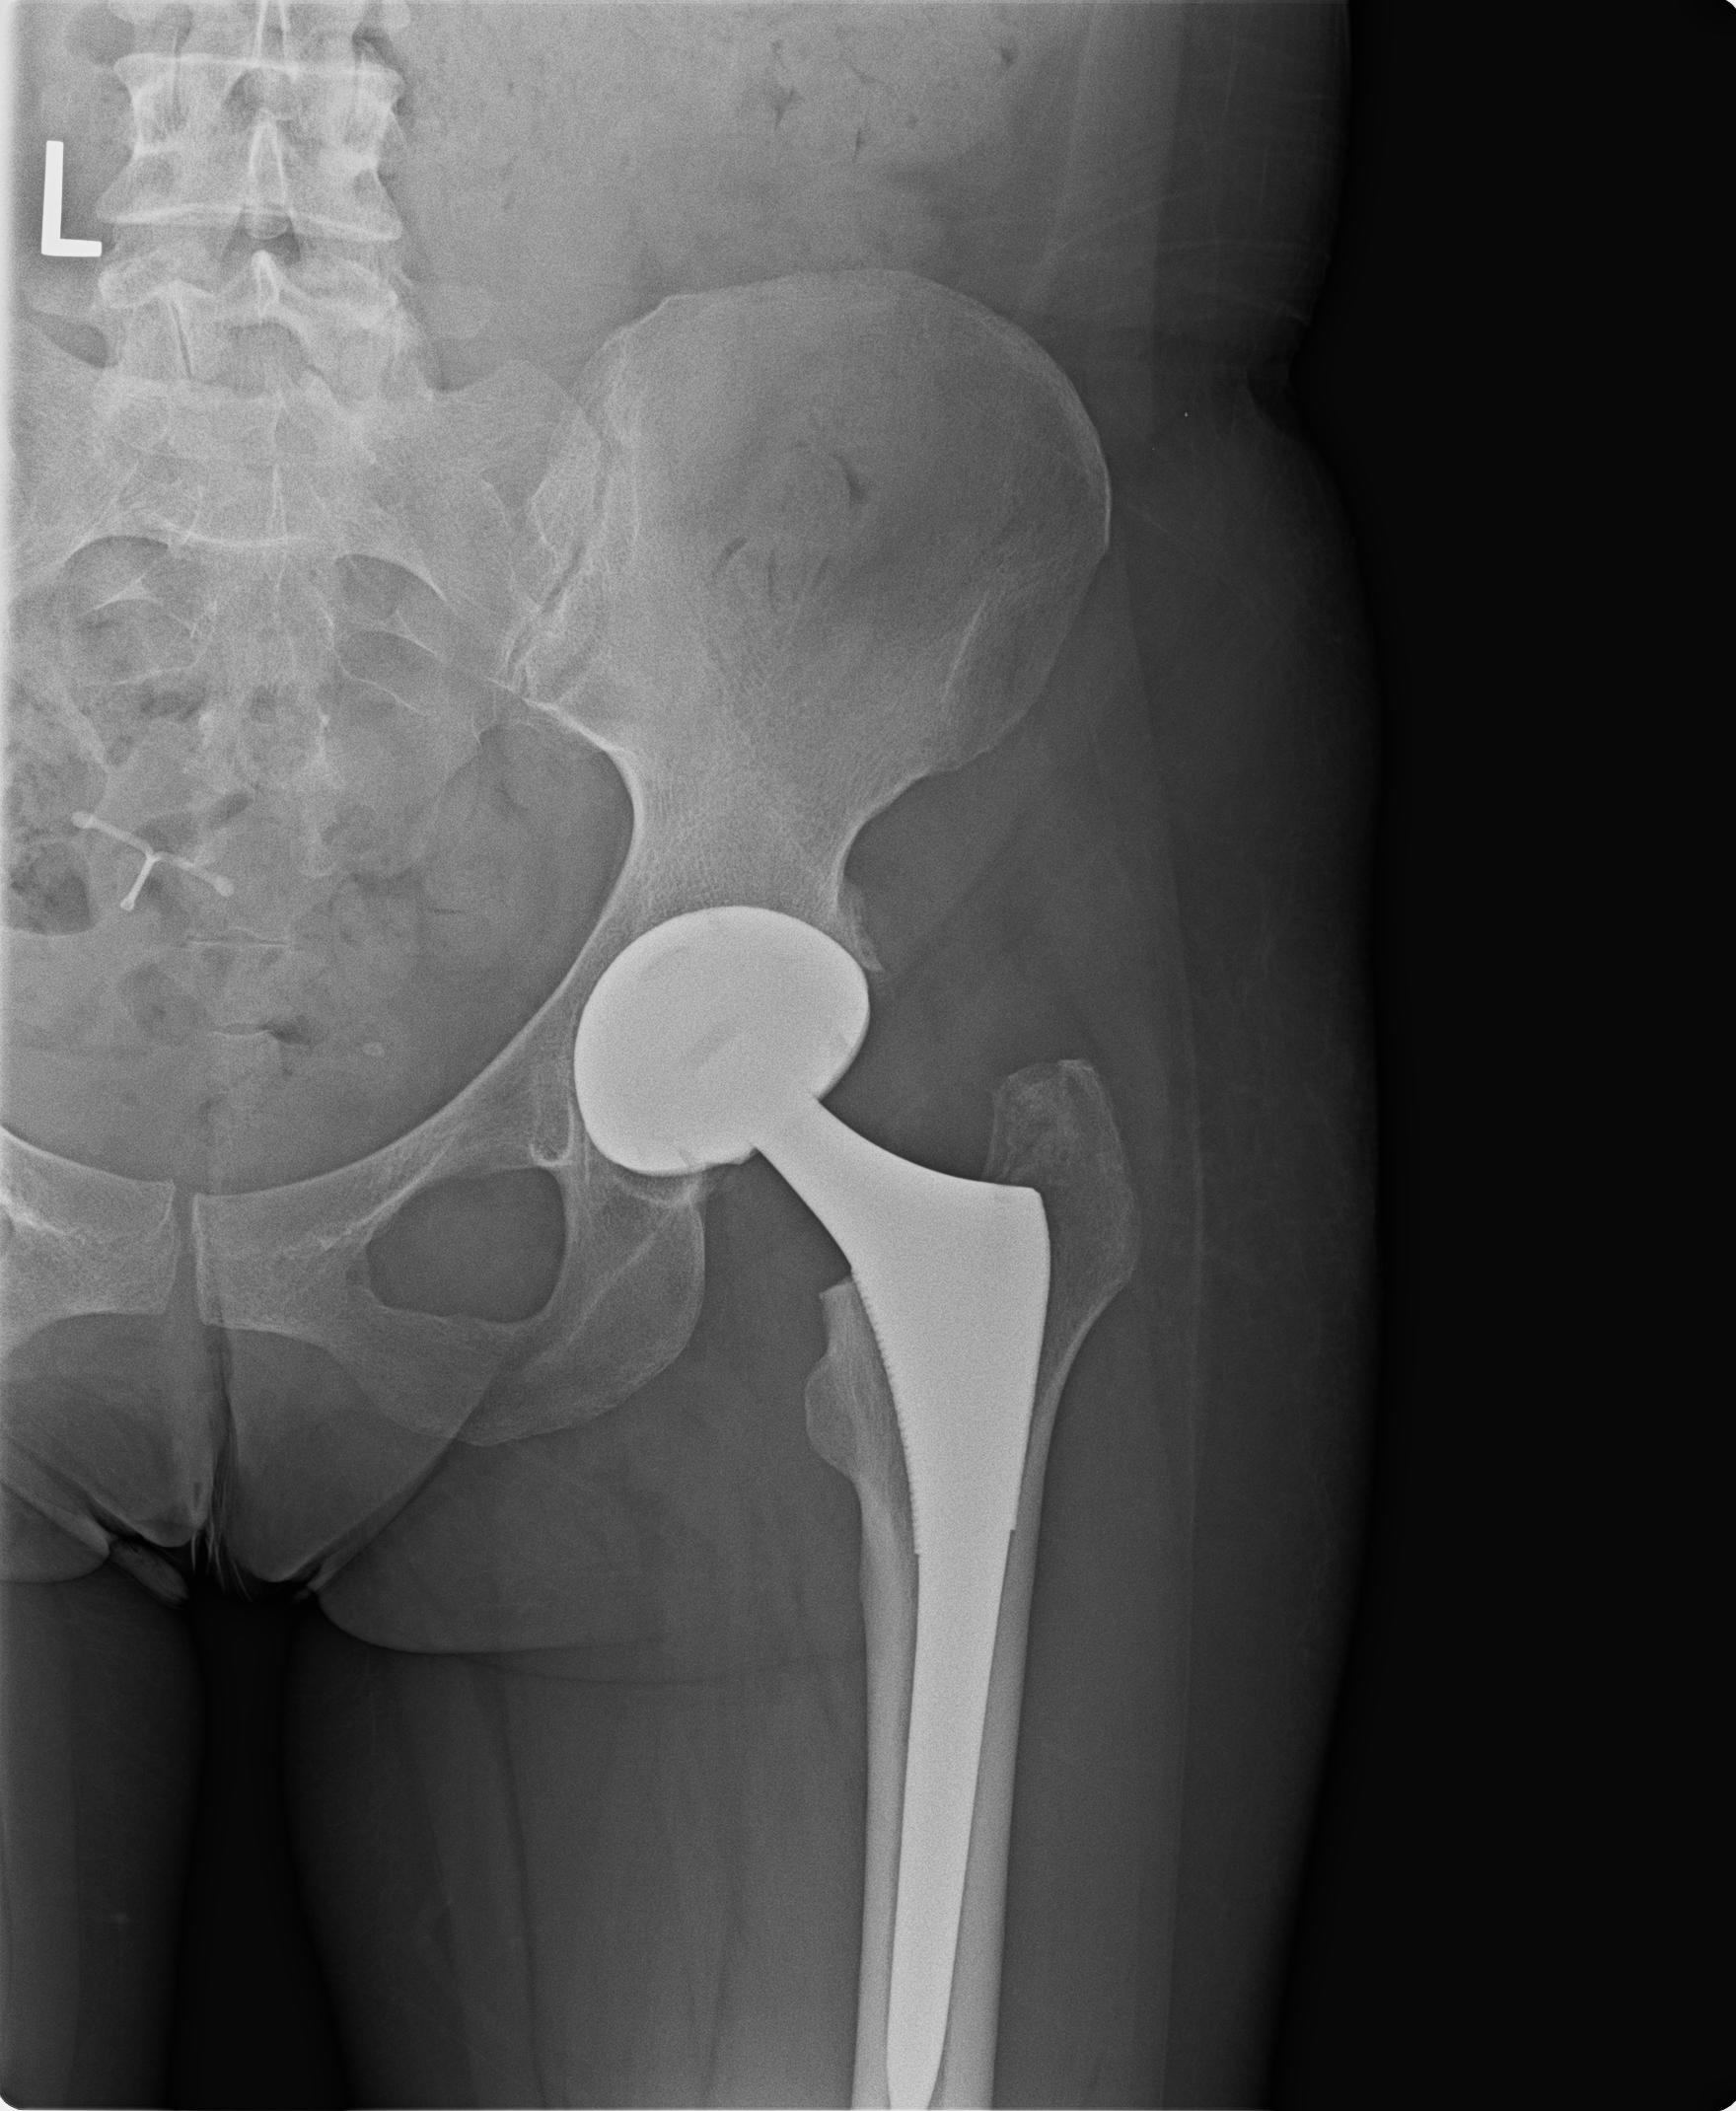

ΕΠΑΝΟΡΘΩΤΙΚΗ ΧΕΙΡΟΥΡΓΙΚΗ - ΙΣΧΙΟ

H άρθρωση του ισχίου είναι μία από τις πιο συνήθεις περιοχές ανάπτυξης οστεοαρθρίτιδας. Οστεοαρθρίτιδα σημαίνει φθορά της άρθρωσης και μπορεί να είναι πρωτοπαθής (ιδιοπαθής) όταν οφείλεται σε άγνωστο αίτιο, ή να είναι δευτεροπαθής, δηλαδή να είναι το αποτέλεσμα άλλης παθολογικής κατάστασης. Και στις δύο περιπτώσεις το αποτέλεσμα είναι το ίδιο: η βαθμιαία καταστροφή του αρθρικού χόνδρου. Η οστεοαρθρίτιδα του ισχίου εμφανίζεται συνήθως σε άτομα ηλικίας άνω των 55 ετών και έχει ως κύρια συμπτώματα πόνο στην περιοχή του ισχίου, που επιδεινώνεται συνήθως τη νύχτα καθώς επίσης και με τις δραστηριότητες. Στις περισσότερες περιπτώσεις υπάρχει και περιορισμός της κινητικότητας. Αρχικά η θεραπεία της νόσου είναι συντηρητική. Στα αρχικά στάδια μπορεί να περιλαμβάνεται ξεκούραση, βάδιση με πατερίτσες, αντιφλεγμονώδη και παυσίπονα φάρμακα. Δυστυχώς με την πάροδο των ετών η νόσος και η φθορά επιδεινώνονται με αποτέλεσμα τα συντηρητικά μέτρα να καθίστανται ανεπαρκή. Στις περιπτώσεις αυτές η θεραπεία είναι χειρουργική και συνίσταται στην ολική αρθροπλαστική του ισχίου. Στην επέμβαση αυτή αντικαθίσταται η μηριαία κεφαλή και η επιφάνεια της κοτύλης με μεταλλικές προθέσεις. Η επέμβαση αυτή συνοδεύεται από πολύ υψηλό ποσοστό επιτυχίας και προσφέρει γρήγορη κινητοποίηση του ασθενή από τις πρώτες μετεγχειρητικές μέρες.